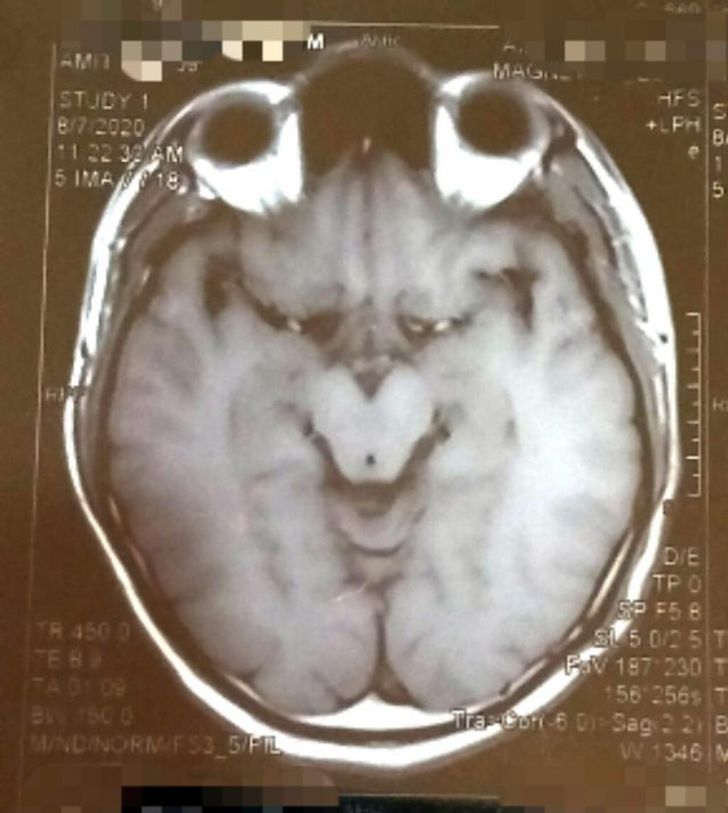

18. Une IRM lui a révélé que le Grinch se cachait dans son cerveau

© indiaisthebestalways / Reddit